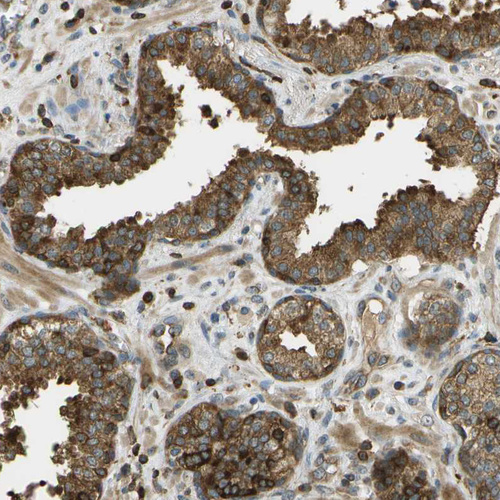

Immunohistochemical staining of human kidney shows strong granular cytoplasmic positivity in cells in tubules and in glomeruli.